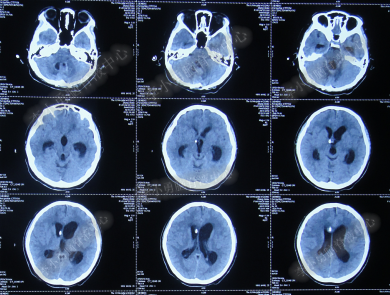

第3次手术右侧脑室外引流术后1个月时间内,脑积水仍没有得到控制,再给予腰大池引流,期间多次试图拔除右侧脑室外引流管(多次调高脑室外引流管的高度),但因患者意识变差,而无法拔除引流管,给予拔除腰大池引流,治疗期间曾多次查头部CT均示脑积水仍无改善(图-20、图-21、图-22、图-23)。

图-20:2014年7月24日头部CT

图-21:2014年7月29日头部CT

图-22:2014年8月4日头部CT

图-23:2014年8月15日头部CT